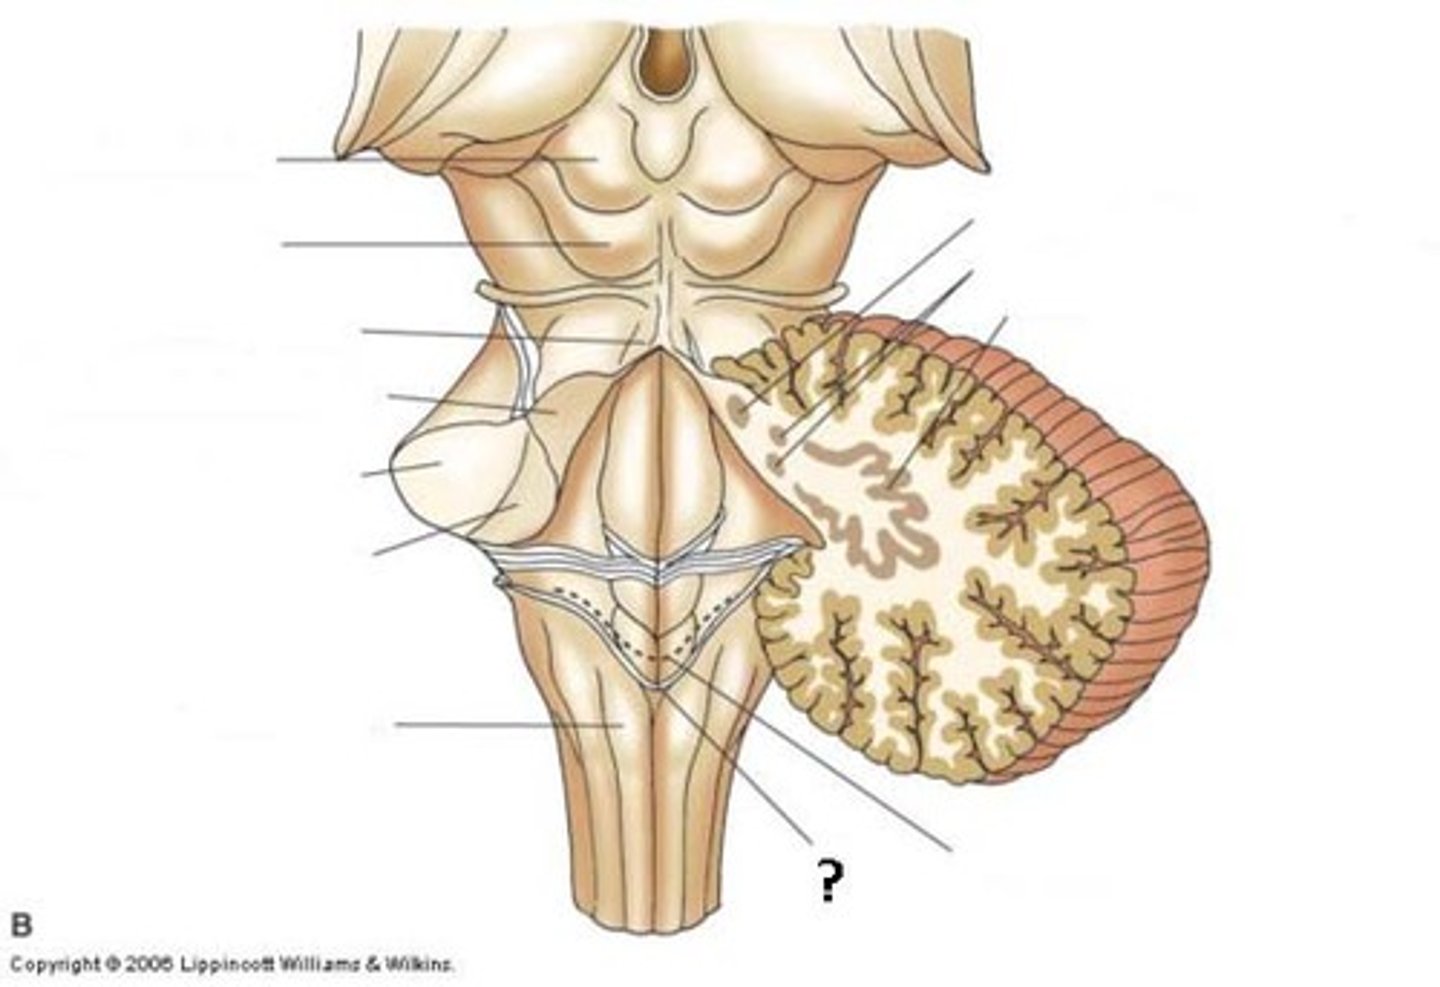

What anatomical aspect of the 4th ventricle is considered its floor?

ventral

refers to the floor of the 4th ventricle

rhomboid fossa

What forms the floor (rhomboid fossa) of the 4th ventricle?

dorsal surfaces of pons tegmentum and open medulla

inferior angle of the floor of the 4th ventricle

obex

vertical groove running in the floor of the 4th ventricle that separates it into right and left halves

dorsal median sulcus

vertical groove lateral to the dorsal median sulcus of the 4th ventricle

**same one that separated the alar and dorsal plates in the neural tube during development

sulcus limitans

refers to most of the floor of the 4th ventricle lateral to the sulcus limitans

**namesake nuclei are here

vestibular area

triangular region located in the caudal portion of the rhomboid fossa of the 4th ventricle, where the dorsal motor nucleus of CN X is

vagal trigone

Which parasympathetic nucleus is found in the vagal trigone of the 4th ventricle?

dorsal motor nucleus of X

triangular region located most medially in the caudal portion of the rhomboid fossa of the 4th ventricle, where the CN XII nucleus is

hypoglossal trigone

part of the 4th ventricle superior to the vagal and hypoglossal trigones (still medial to the sulcus limitans)

medial eminence

small bump located in the caudal portion of the medial eminence which forms from the motor fibers of CN VII as they wind around the underlying CN VI nucleus

facial colliculus

What anatomical aspect of the 4th ventricle is considered its roof?

dorsal

What forms the superior portion of the roof of the 4th ventricle? (A)

superior cerebellar peduncles

inverted V shaped interval between the superior cerebellar peduncles that is filled by a thin layer of white matter

superior medullary velum

lower portion of the roof of the 4th ventricle formed by a thin layer of pia mater and ependymal cells

inferior medullary velum

structure attached to the ventral surface of the inferior medullary velum in the 4th ventricle that helps form CSF

choroid plexus

opening in the caudal aspect of the inferior medullary velum that allows CSF from the 4th ventricle to flow into the cisterna magna of the subarachnoid space

foramen of Magendie (or median aperture)

What mostly forms the lateral walls of the 4th ventricle?

inferior cerebellar peduncles and choroid plexus

openings in the 4th ventricle that allows CSF to flow from the 4th ventricle into the pontine cistern of the subarachnoid space

foramen of von Luschka (or lateral apertures)

floor of 4th ventricle

rhomboid fossa

sulcus limitans

floor of 4th ventricle lateral to sulcus limitans

vestibular area

vasal trigone

hypoglossal trigone

medial eminence

small bump in caudal portion of medial eminence

facial colliculus

stria medullares

A

superior cerebellar peduncles

superior medullary velum

inferior medullary velum